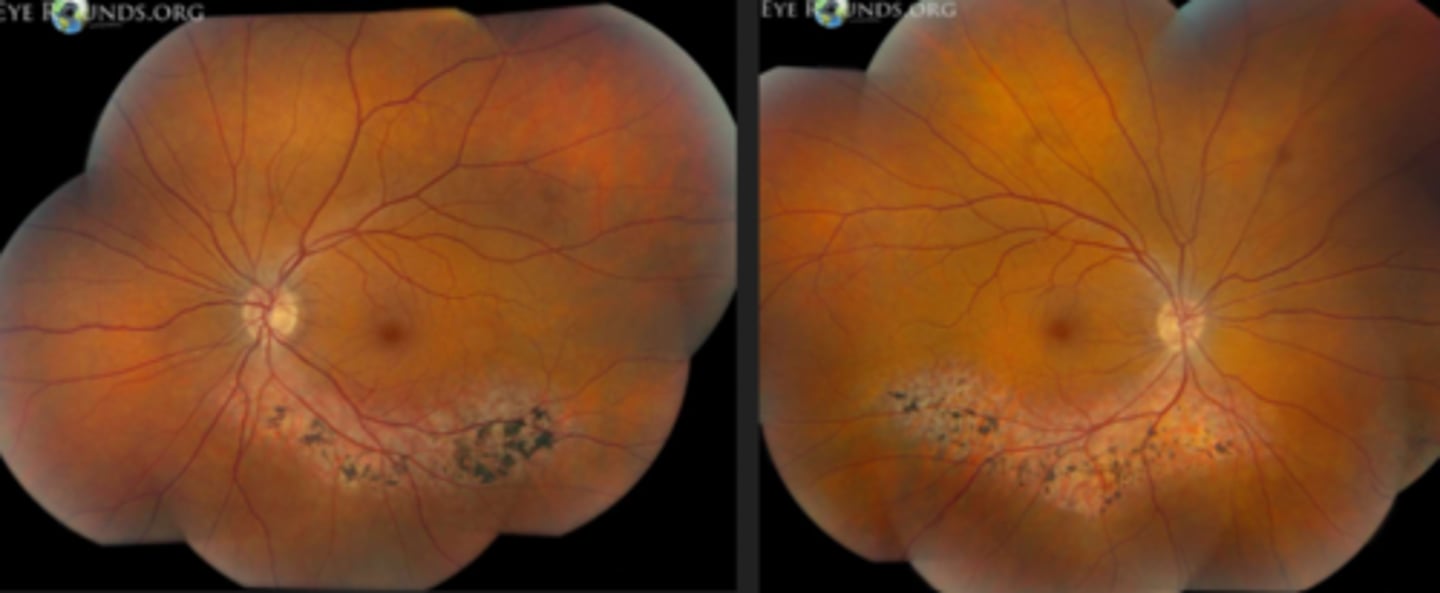

What findings of Leber's Congenital Amaurosis are seen here?

attenuated BV

peripheral pigmentary changes

FAF = peripheral hypopigmented spots and a ring of hyperfluorescence surrounding the fovea

macular atrophic lesion